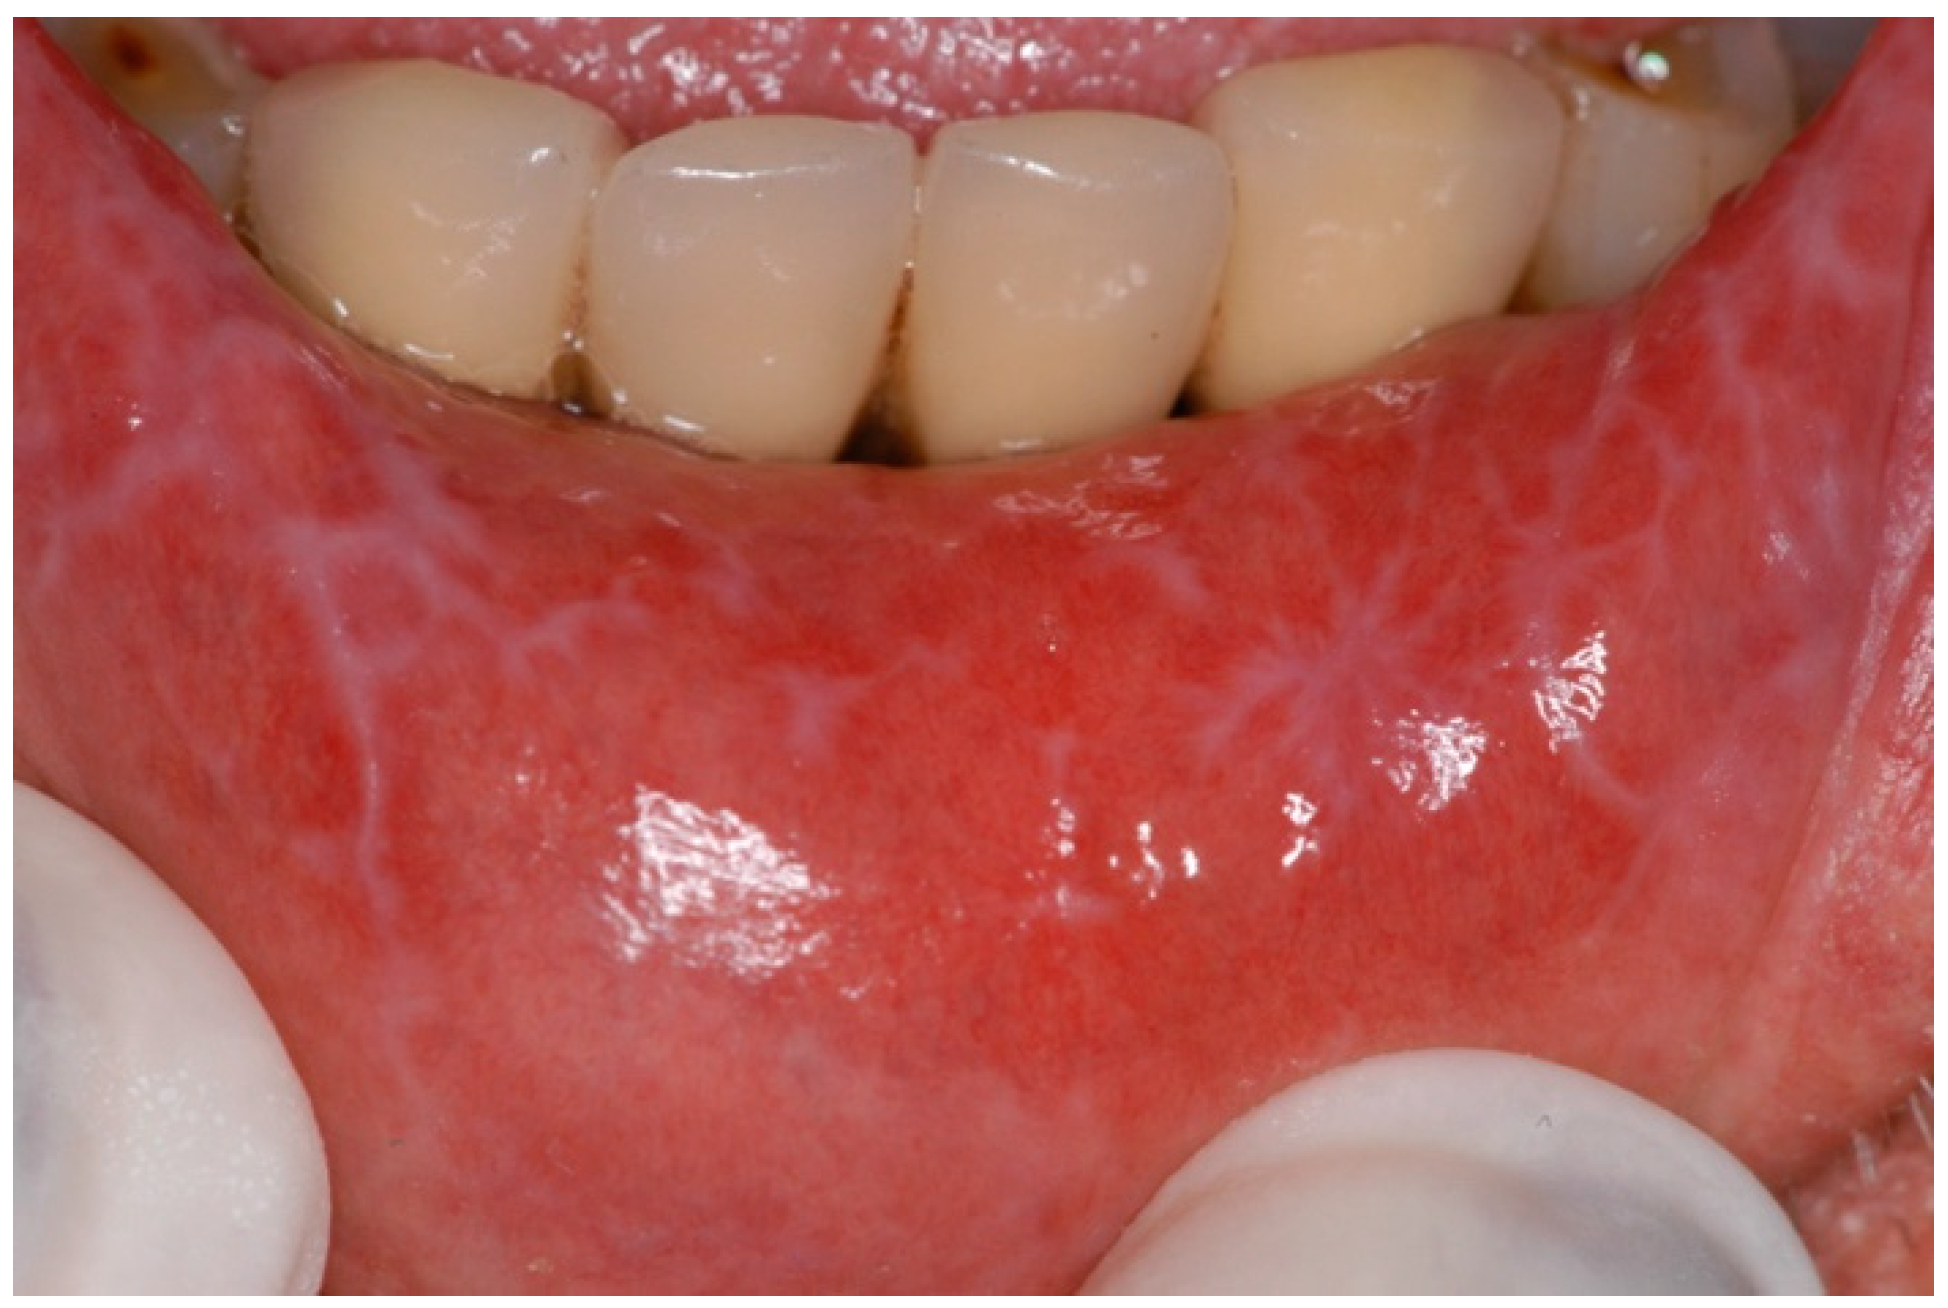

2.1.2. Oral Lichenoid Lesions (OLLs)